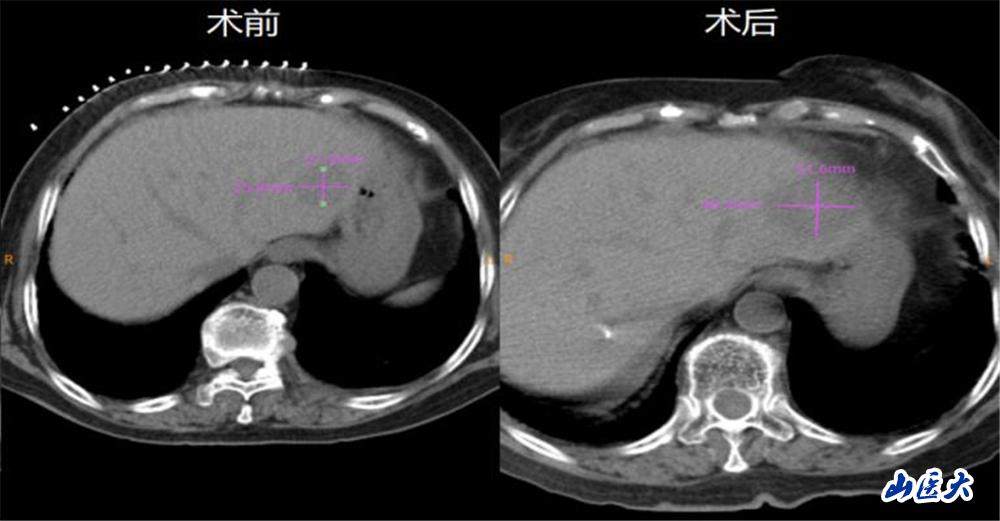

在介入手术室魏臻护士长带领的护理团队配合下,肿瘤科微创治疗团队成功为该患者进行了CT引导下经皮肝S2段转移瘤微波消融治疗。对比术前术后CT,消融范围明确,且超出原并发灶边缘5mm以上,达到了完全消融的效果。